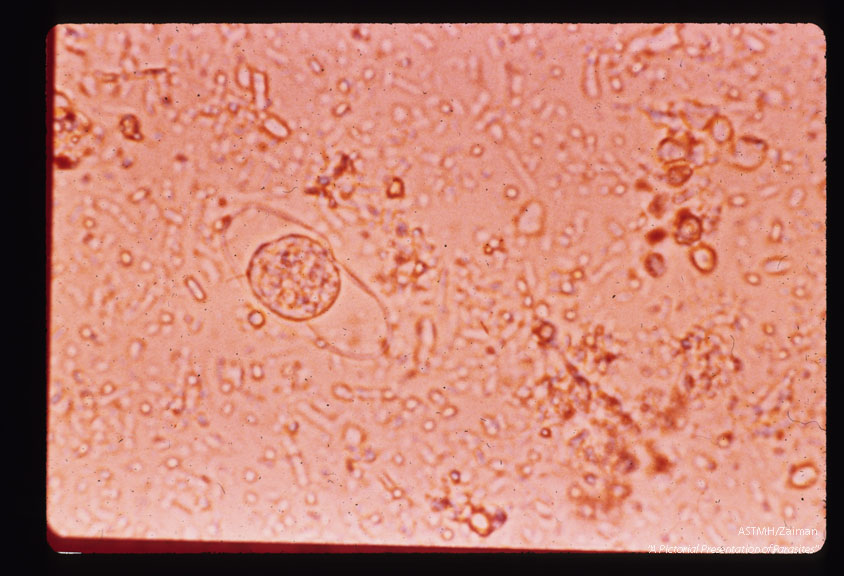

Oocyst with single protoplasmic mass.

Isospora belli

Description: Oocyst with single protoplasmic mass.